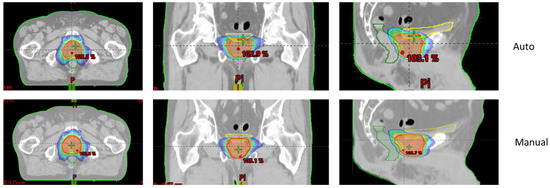

Figure 1 and Figure 2 show an example of dose distributions comparing automated and manual treatment plans for prostate-only localization. Another example for whole-pelvic irradiation is shown in Supplementary Materials Figures S1–S3.

Figure 1. Example of 76 Gy isodose for automated (upper—“Auto”) and manual (lower) treatment plans for prostate-only localization (Patient n° 7).